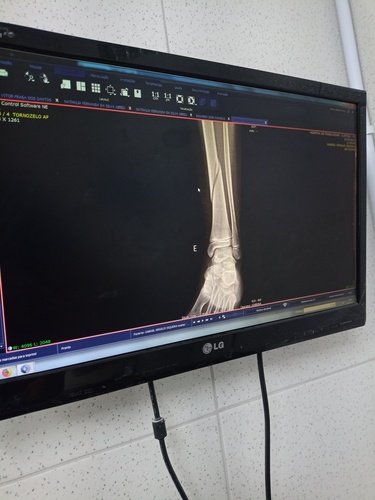

Gabriel estuda no 7° ano no colégio cívico militar Gottbier Muller , no dia 22/09 , uma professora não foi e a turma ficou com aula vaga, nisso liberaram as crianças pro pátio , sozinhos sem supervisão de um adulto, nisso, ele e mais duas crianças( um menino e uma menina) ficaram sentados , até que essa menina , pediu pra ele a acompanhá-la, nisso ela o abraça e começa a dar chutes em sua perna , meu filho ficou com a perna firme pra não sair , até que no terceiro ou quarto chute ele sai com muita dor , cai ajoelhado , e logo após começa a se bater de muita dor ( tipo tendo convulsões) …. Ai, só depois disso que uma professora viu e vai olhar o que estava acontecendo….. um outro menininho da turma resolveu ir chamar meu filho mais velho que também estuda no mesmo colégio, e só depois que foram atrás de monitor, pedagoga , enfim dos responsáveis. Um dos monitores militares, resolve massagear o tornozelo, pois achou que ele tinha torcido o pé , e só depois que acionaram o siate e me ligaram. O siate nós atendeu, e o encaminhou para o hospital do trabalhador, lá foi feito raio-x e mostrou que ele quebrou a tíbia em dois lugares. No dia 03/10 tive retorno médico, o dr° pediu repouso absoluto, pra tentar calcificar, mas que tudo indica que terá que operar…. Meu filho tem 11 anos e por essa situação está tendo que usar fraldas, banho só de paninho.…. Estou tento muitos gastos , e nem o colégio , nem a família da menina está me ajudando…. Sou autônoma, se não trabalho não ganho, e quase não estou conseguindo trabalhar , por isso que resolvi fazer essa vaguinha,pra que eu possa pagar as contas da casa, manter os cuidados com ele .